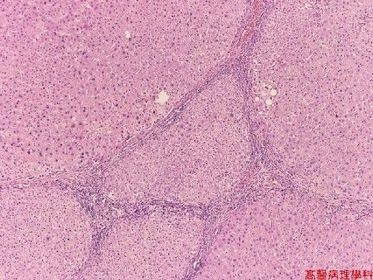

TISSUE TYPE: O.o (loss of architecture) PATHOLOGY: thick fibrous speta with inflamatory cells .. separate nodules of undefined cells. (steatosis) Diagnosis: liver cirrhosis xD KEY: CAN'T SEE ANY SPECIAL THING ABOUT LIVER CAUSE ACTULLAY IT'S DEAD :D

liver cirrhosis